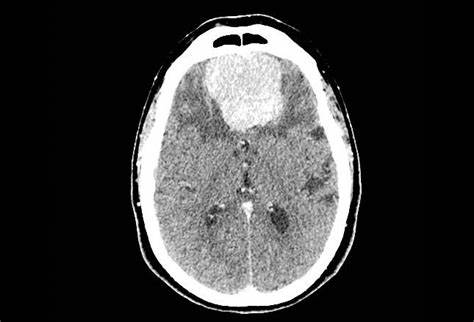

脑膜瘤和其他中枢神经系统肿瘤一样,取决于其位置。脑膜瘤可见于任何颅内或脊膜表面。很少,脑室内脑膜瘤被发现。脑膜瘤通常不是快速生长或浸润性病变,有隐匿的症状。许多是在大脑成像中偶然发现的。虽然没有脑膜瘤的病理学表现,但典型的临床症状是颅内压升高、局灶性神经(包括颅神经)缺损或局灶性肿块效应引起的全身性和部分性癫痫发作。人格改变、意识混乱和意识水平改变,是在前(额)或矢状窦旁脑膜瘤中,较初可能被误诊为痴呆或抑郁症。有这种症状的病人的鉴别诊断相当广泛,应该包括其他颅内病变(如胶质瘤或转移瘤)。

对于病人和临床医生来说,一个重要的问题是肿瘤的自然病程,是在偶然发现时。虽然活检或切除是确定诊断的方法,但通过组织病理学分析,典型的放射学表现通常就足够了,仍然是诊断脑膜瘤较常用的技术(见“脑膜瘤的放射诊断和影像学特征及前沿成像的作用”一节)。一些观察研究显示无症状脑膜瘤的线性增长率为2-4毫米/年。然而,一些肿瘤显示出非线性的指数增长模式或根本没有增长,这就强调了在未经治疗的患者中进行监视成像的重要性。此外,人们认为较大的有症状的脑膜瘤有着不同的自然病史和更具侵袭性的生长模式,但由于这些肿瘤很少未经治疗,其的自然病史还不清楚。